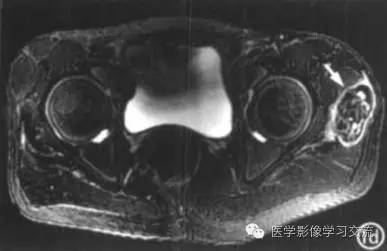

其它检查结果如下:

MRI具有多参数、多序列、多方位成像的功能,可根据信号判断组织成分; 由于肿瘤主要由纤维包膜包裹的钙化沉积物及淡黄色乳糜状液体组成,内有纤维间隔,

因此 T1WI肿瘤呈不均匀低信号, T2WI 呈不均匀高信号; 肿瘤包膜呈长 T1 、长 T2 信号。MRI 对观察肿瘤边缘及肿瘤与关节、骨骼的关系价值大,能多方位显

示病变不累及关节或骨骼,对诊断有较大帮助。